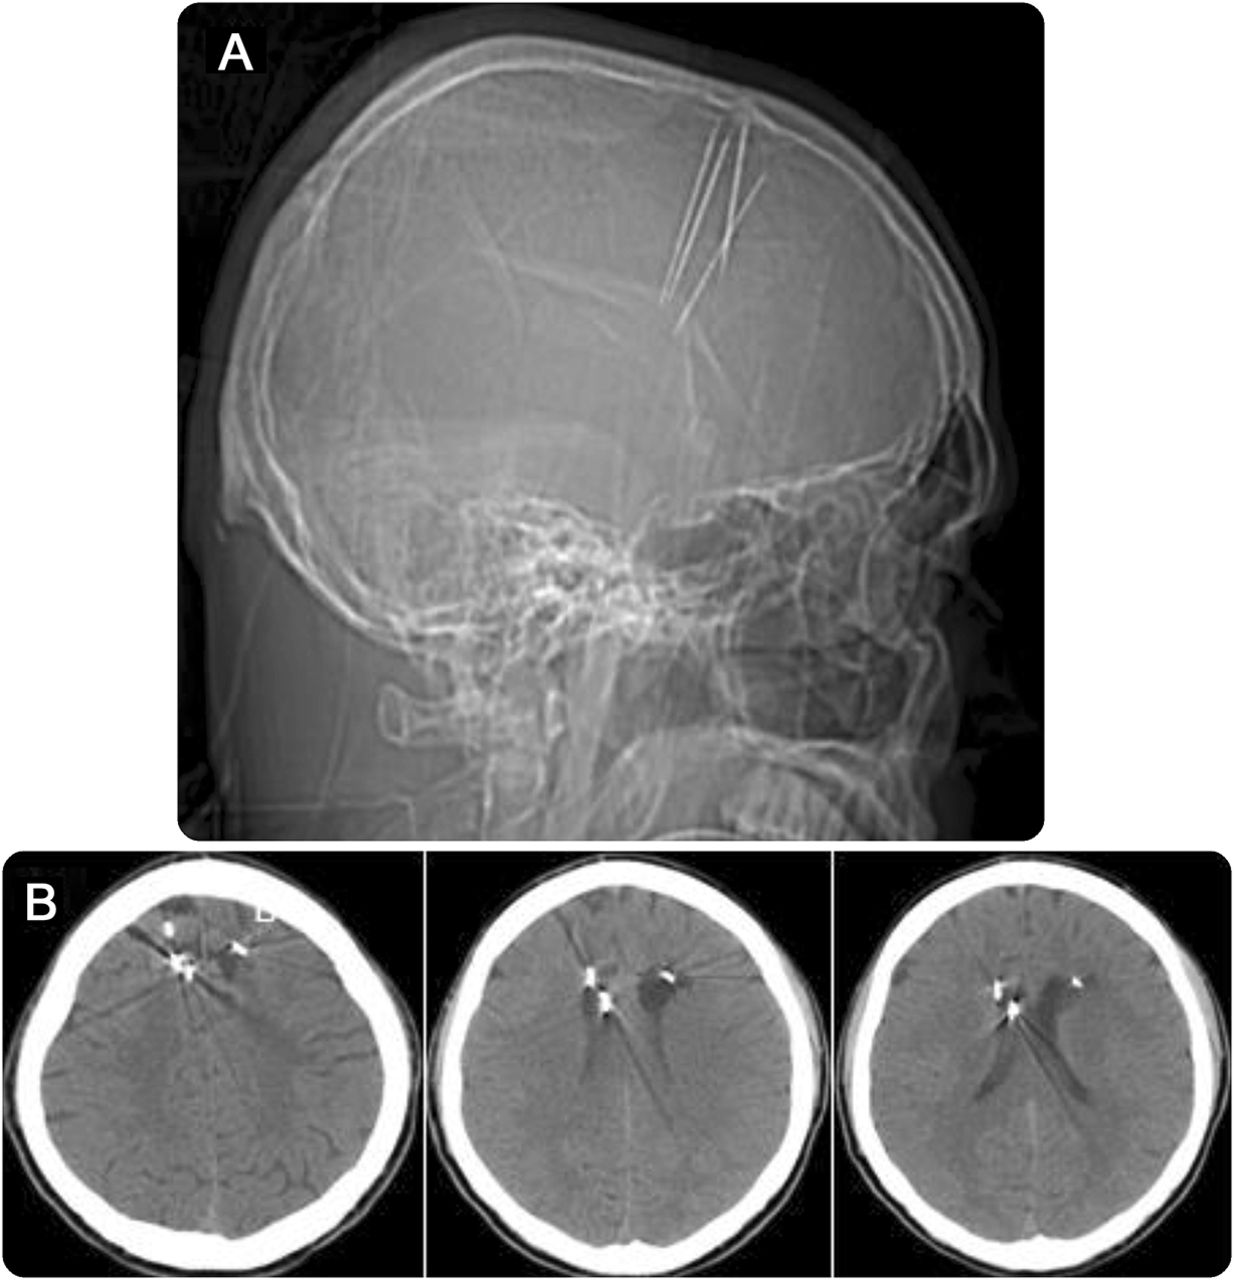

一个29岁的南亚人,从小与癫痫,癫痫发作的急诊室。CT扫描(图)显示多个金属针从冠状缝投射到大脑。为了驱逐恶魔,传统治疗师相信困扰病人,颅骨和脑与针头刺穿。目前尚不清楚魔鬼成功驱逐,但癫痫持续,可能恶化了这种治疗。措施是必要的警告公众不要危险的传统医学模式。1,2